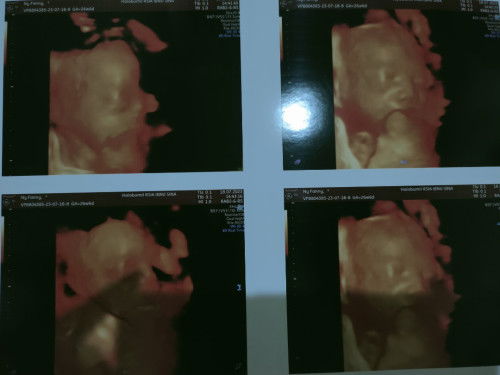

Plasenta ankreta atau sisa lengket.

Mom aku mau crita aku kan lahiran anak prtama riwayat plasenta ankreta plasenta kluar tp masi ada sisa di rahim jd hrus kuret. Kemudian sya ini hamil anak ke 2 kmrin sya USG trus tanya dokternya ktanya ada kemungkinan sma kelahiran anak ke 2. Gmana ya bund dsni ada yg lahir brikutnya normal aj atau ttep plasenta lengket .. trimksih mhon dijwb ya mom#seriusnanya #bantusharing #ingintahu #firstmom #pleasehelp #firstbaby